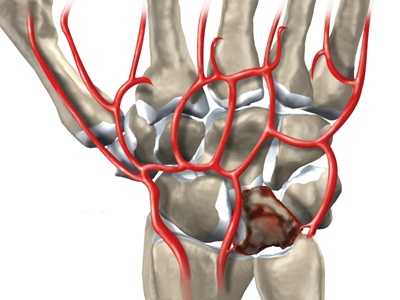

Некроз полулунной кости при болезни Кинбека

Дегенеративные изменения кости провоцируются ухудшением локального кровоснабжения вследствие перегрузки и травматических повреждений. Вокруг очага дегенерации образуется зона отека, что также негативно влияет на местное кровообращение. Процессы разрушения превалируют над процессами восстановления. Из-за поражения значительной части кости даже при небольших травматических воздействиях возникают патологические переломы.

На фоне импрессионных переломов продолжает снижаться прочность костной ткани. На суставной поверхности образуются участки некроза и фиброзного перерождения, деформации усугубляются. Кость фрагментируется. Суставные поверхности утрачивают конгруэнтность, прогрессируют артрозные изменения. Степень окончательной деформации варьируется от незначительной до грубой.